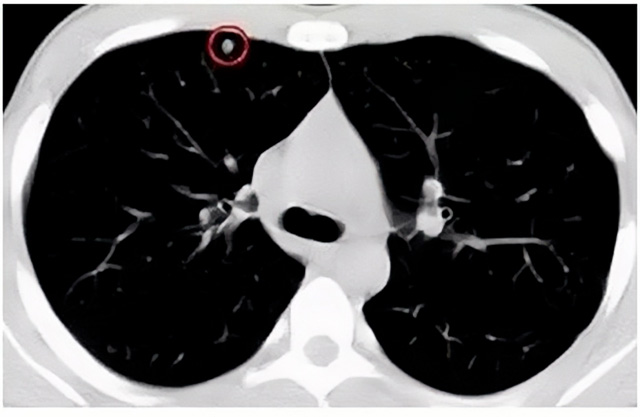

移动CT体检车可以检查肺结节发现早期肺癌

移动CT体检车可以做肺部检查。随着多层螺旋CT肺部低剂量扫描的临床应用,目前很多人选择肺部CT作为常规检查项目,较大地提高了肺结节的检出率。如果检查发现肺部有肺结节是磨玻璃型的,小于5mm的微小结节,大部分都是良性的。如果达到1CM以上的,很有可能有肺癌的机率。根据其内密度不同可分为磨玻璃结节、实性结节、部分实性结节。根据其大小可分为肺大结节、小结节和微小结节。如果是炎症性肺结节,几个月后复查有变化变小就不用做手术。如果CT再次复查结节没有变化,没有缩小就需要升级做病例检查。病理检查的确诊性是最高的。是有没患癌的标准。检查发现早的话,规范手术治疗,手术后5年的存活率很高的。肺癌这个要早发现早治疗。

现在的移动CT体检车的分辨率比X光高,CT扫描的图像越来越薄显像更清晰,检查更准确。得到了普及,肺结节的测出率很高的。但是显浩告诉大家,肺结节不等于肺癌。虽然很多是良性,但是很多肺癌都是肺结节发展来的。 必须定期检查复查。磨玻璃结节,肺癌的机率较高。肺癌是恶性肿瘤病死率最高的。除了环境,遗传,等因素。吸烟,从事烟雾工作行业的人员比较危险。发病比例高。肺部疾病早发现早治疗,依旧是肺部疾病的治疗标准。

一旦CT检查发现肺结节,若不规律复查,检查等同于白检。所以在复查中,如果结节中发现有增大的趋势,或大小发生了变化,我们必须提请注意及时治疗,不要掉以轻心。移动CT体检车的普及化,让肺部检查更准确更高效。发现肺结节时,及时就医并进行专业评估是确保准确分类和采取适当措施的关键。